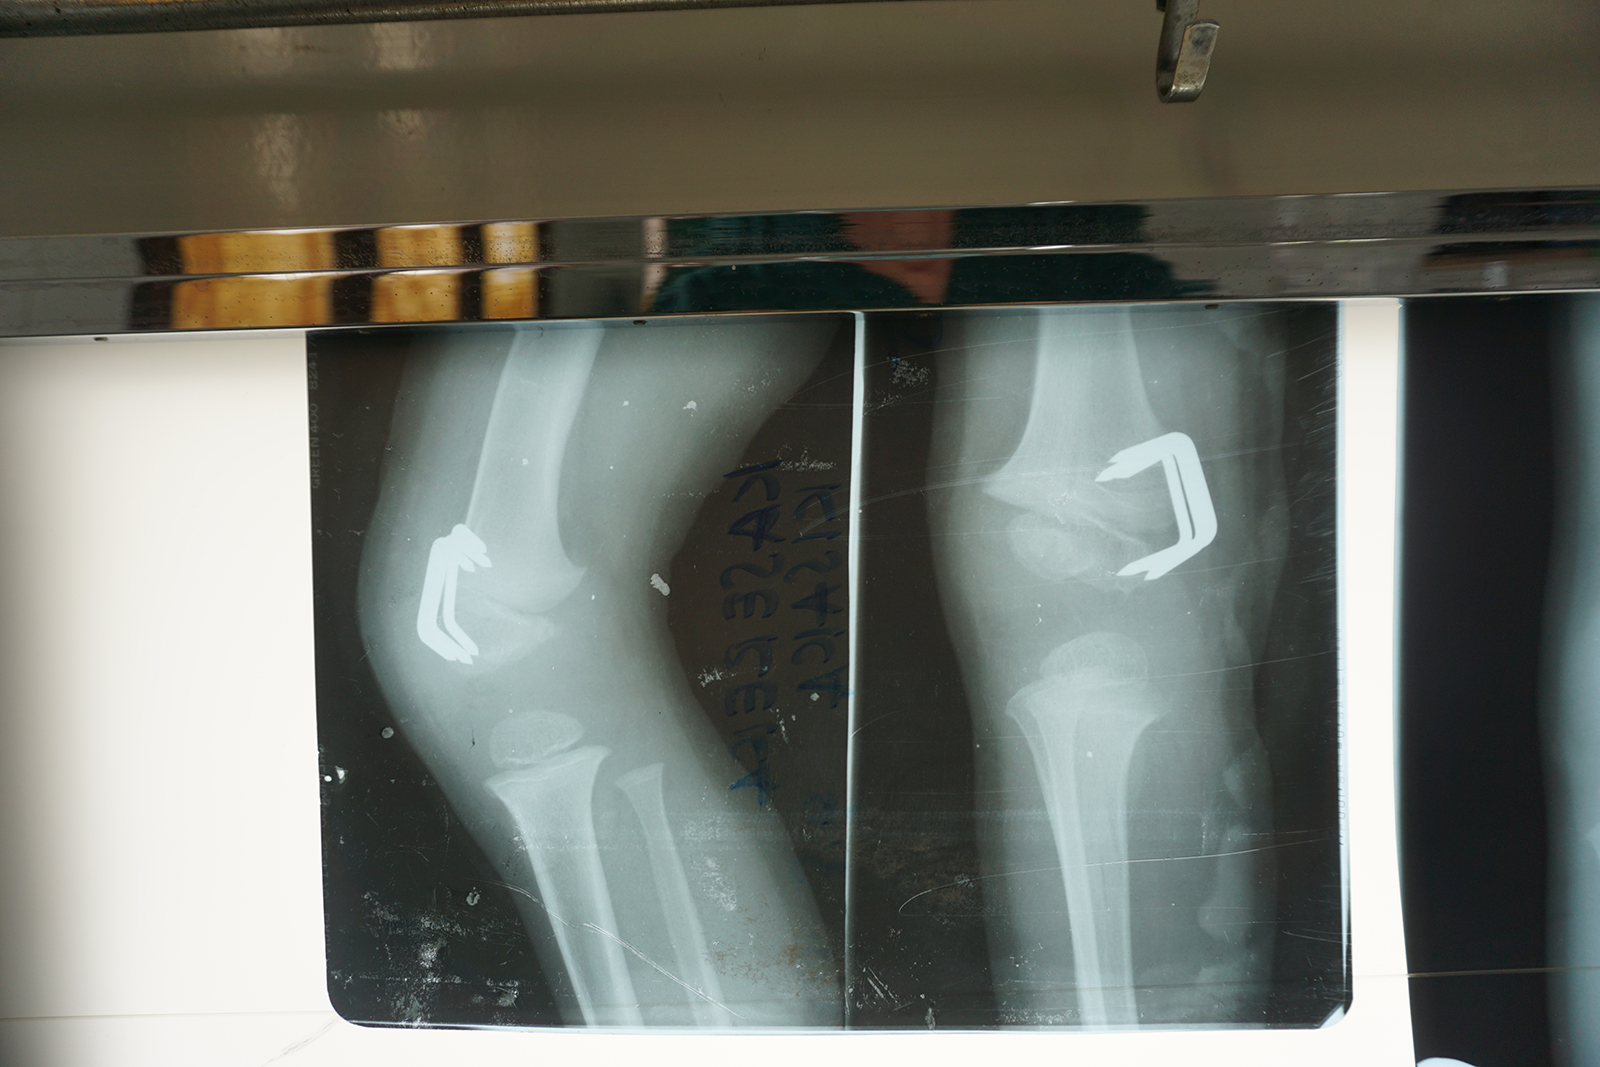

Wird das Wachstum auf einer Seite einer solchen Fuge gezielt gebremst, wächst der Knochen auf der gegenüberliegenden Seite weiter. Dadurch kann sich eine Achsfehlstellung über Monate oder Jahre allmählich selbst korrigieren. Die Wachstumshemmung erfolgt durch kleine Klammern oder Plättchen, die die Wachstumsfuge überbrücken und so deren Aktivität einschränken (Abb. 4).

Bei Arielle brachten wir im August 2017 Klammern an der Außenseite des rechten Kniegelenkes an, um die O-Bein-Stellung zu korrigieren (Abb. 5). Nach einigen Monaten war die Achsfehlstellung ausreichend ausgeglichen. Es blieb jedoch weiterhin die Überlänge des rechten Beines bestehen.

Um dieses Längenproblem zu behandeln, wurden im August 2018 zusätzlich Klammern an der Innenseite derselben Wachstumsfuge eingesetzt (Abb. 6). Dadurch wurde das Wachstum des rechten Beines insgesamt verlangsamt, ohne es vollständig zu stoppen. Andere Wachstumsfugen blieben weiterhin aktiv, jedoch wuchs das behandelte Bein nun langsamer als das unbehandelte linke. Auf diese Weise erhielt das linke Bein die Möglichkeit, im Wachstum aufzuholen.

Klammern an der Außenseite des rechten Kniegelenkes, November 2017

Korrektur O-Bein-Stellung, November 2017

August 2018